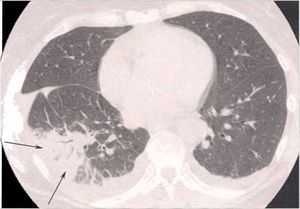

Известно, что острое или хроническое альвеолярное/бронхиальное воспаление является ключевым фактором в развитии патогенеза многих легочных патологий, таких как бронхиальная астма, ХОБЛ, респираторный дистресс-синдром взрослых, идиопатический фиброз легких. Локализация и специфические особенности воспалительного ответа могут быть различными для каждого из этих заболеваний, однако, для всех них характерно привлечение в легочную ткань и активация воспалительных клеток. Эти активированные клетки могут продуцировать цитокины, оксиданты и многие другие медиаторы, которые вовлечены в воспаление 1.

Основу патогенеза ХОБЛ составляет хроническое, диффузное, неаллергическое воспалительное поражение дыхательных путей, которое проходит с участием нейтрофилов, с повышенной активностью миелоперексидазы, нейтрофильной эластазы, металлопротеиназ. Воспалительная реакция связана с нейтрофильной инфильтрацией в очаге воспаления при повышенной активности интерлейкинов-6 и -8 и фактора некроза опухоли-альфа (TNF-альфа) 5. Процесс воспаления имеет многофакторную природу и представляет собой сложную систему взаимодействия клеток воспаления, продуцируемых ими цитокинов и факторов роста, а также активации рецепторного ответа каждой группы клеток, вовлеченных в воспалительный процесс. Повышение симпатической активности у больных ХОБЛ способствует активации ренин-ангиотензин-альдостероновой системы (РААС) и других нейрогормонов и медиаторов (цитокинов, эндотелинов, вазопрессина и др.).